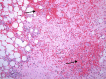

BACKGROUND Myelolipoma is a benign tumor, commonly found in the supra-renal gland, which is composed of mature fatty tissue admixed with hematopoietic elements. However, there are several extra-adrenal sites reported in the literature and thoracic myelolipoma is an unusual location for extra-adrenal myelolipoma. CASE REPORT We present the case of a 71-year-old man previously diagnosed with hypertension who was admitted due to a motor vehicle injury with a lumbar spine fracture. The patient developed non-ST segment elevation myocardial infarction during admission. A coronary angiogram revealed three-vessel disease. Triple coronary artery bypass grafting (CABG) surgery was planned. Upon opening the chest through median sternotomy, a retrosternal adherent mass was incidentally discovered. The mass was excised and histopathological evaluation showed it was myelolipoma in the anterior part of the mediastinum. CONCLUSIONS It is well known that myelolipoma occurs in extra-adrenal sites, and is rarely found at unexpected site, as in our case, which was found incidentally at the anterior mediastinum. With an extensive literature review, we found only 1 case located in the anterior mediastinum. It is crucial to know that myelolipoma can occur in the anterior mediastinum to avoid pitfalls with other differential diagnoses, especially when it is found incidentally and requires a frozen section examination, as it is difficult to diagnose through radiologic imaging only because it can overlap with tumors that are rich in either adipose tissue or hematopoietic elements. However, it affects patient management, and patients usually need only follow-up instead of going through invasive procedures for resection of non-functional tumors, especially in older patients or patients with comorbid diseases.